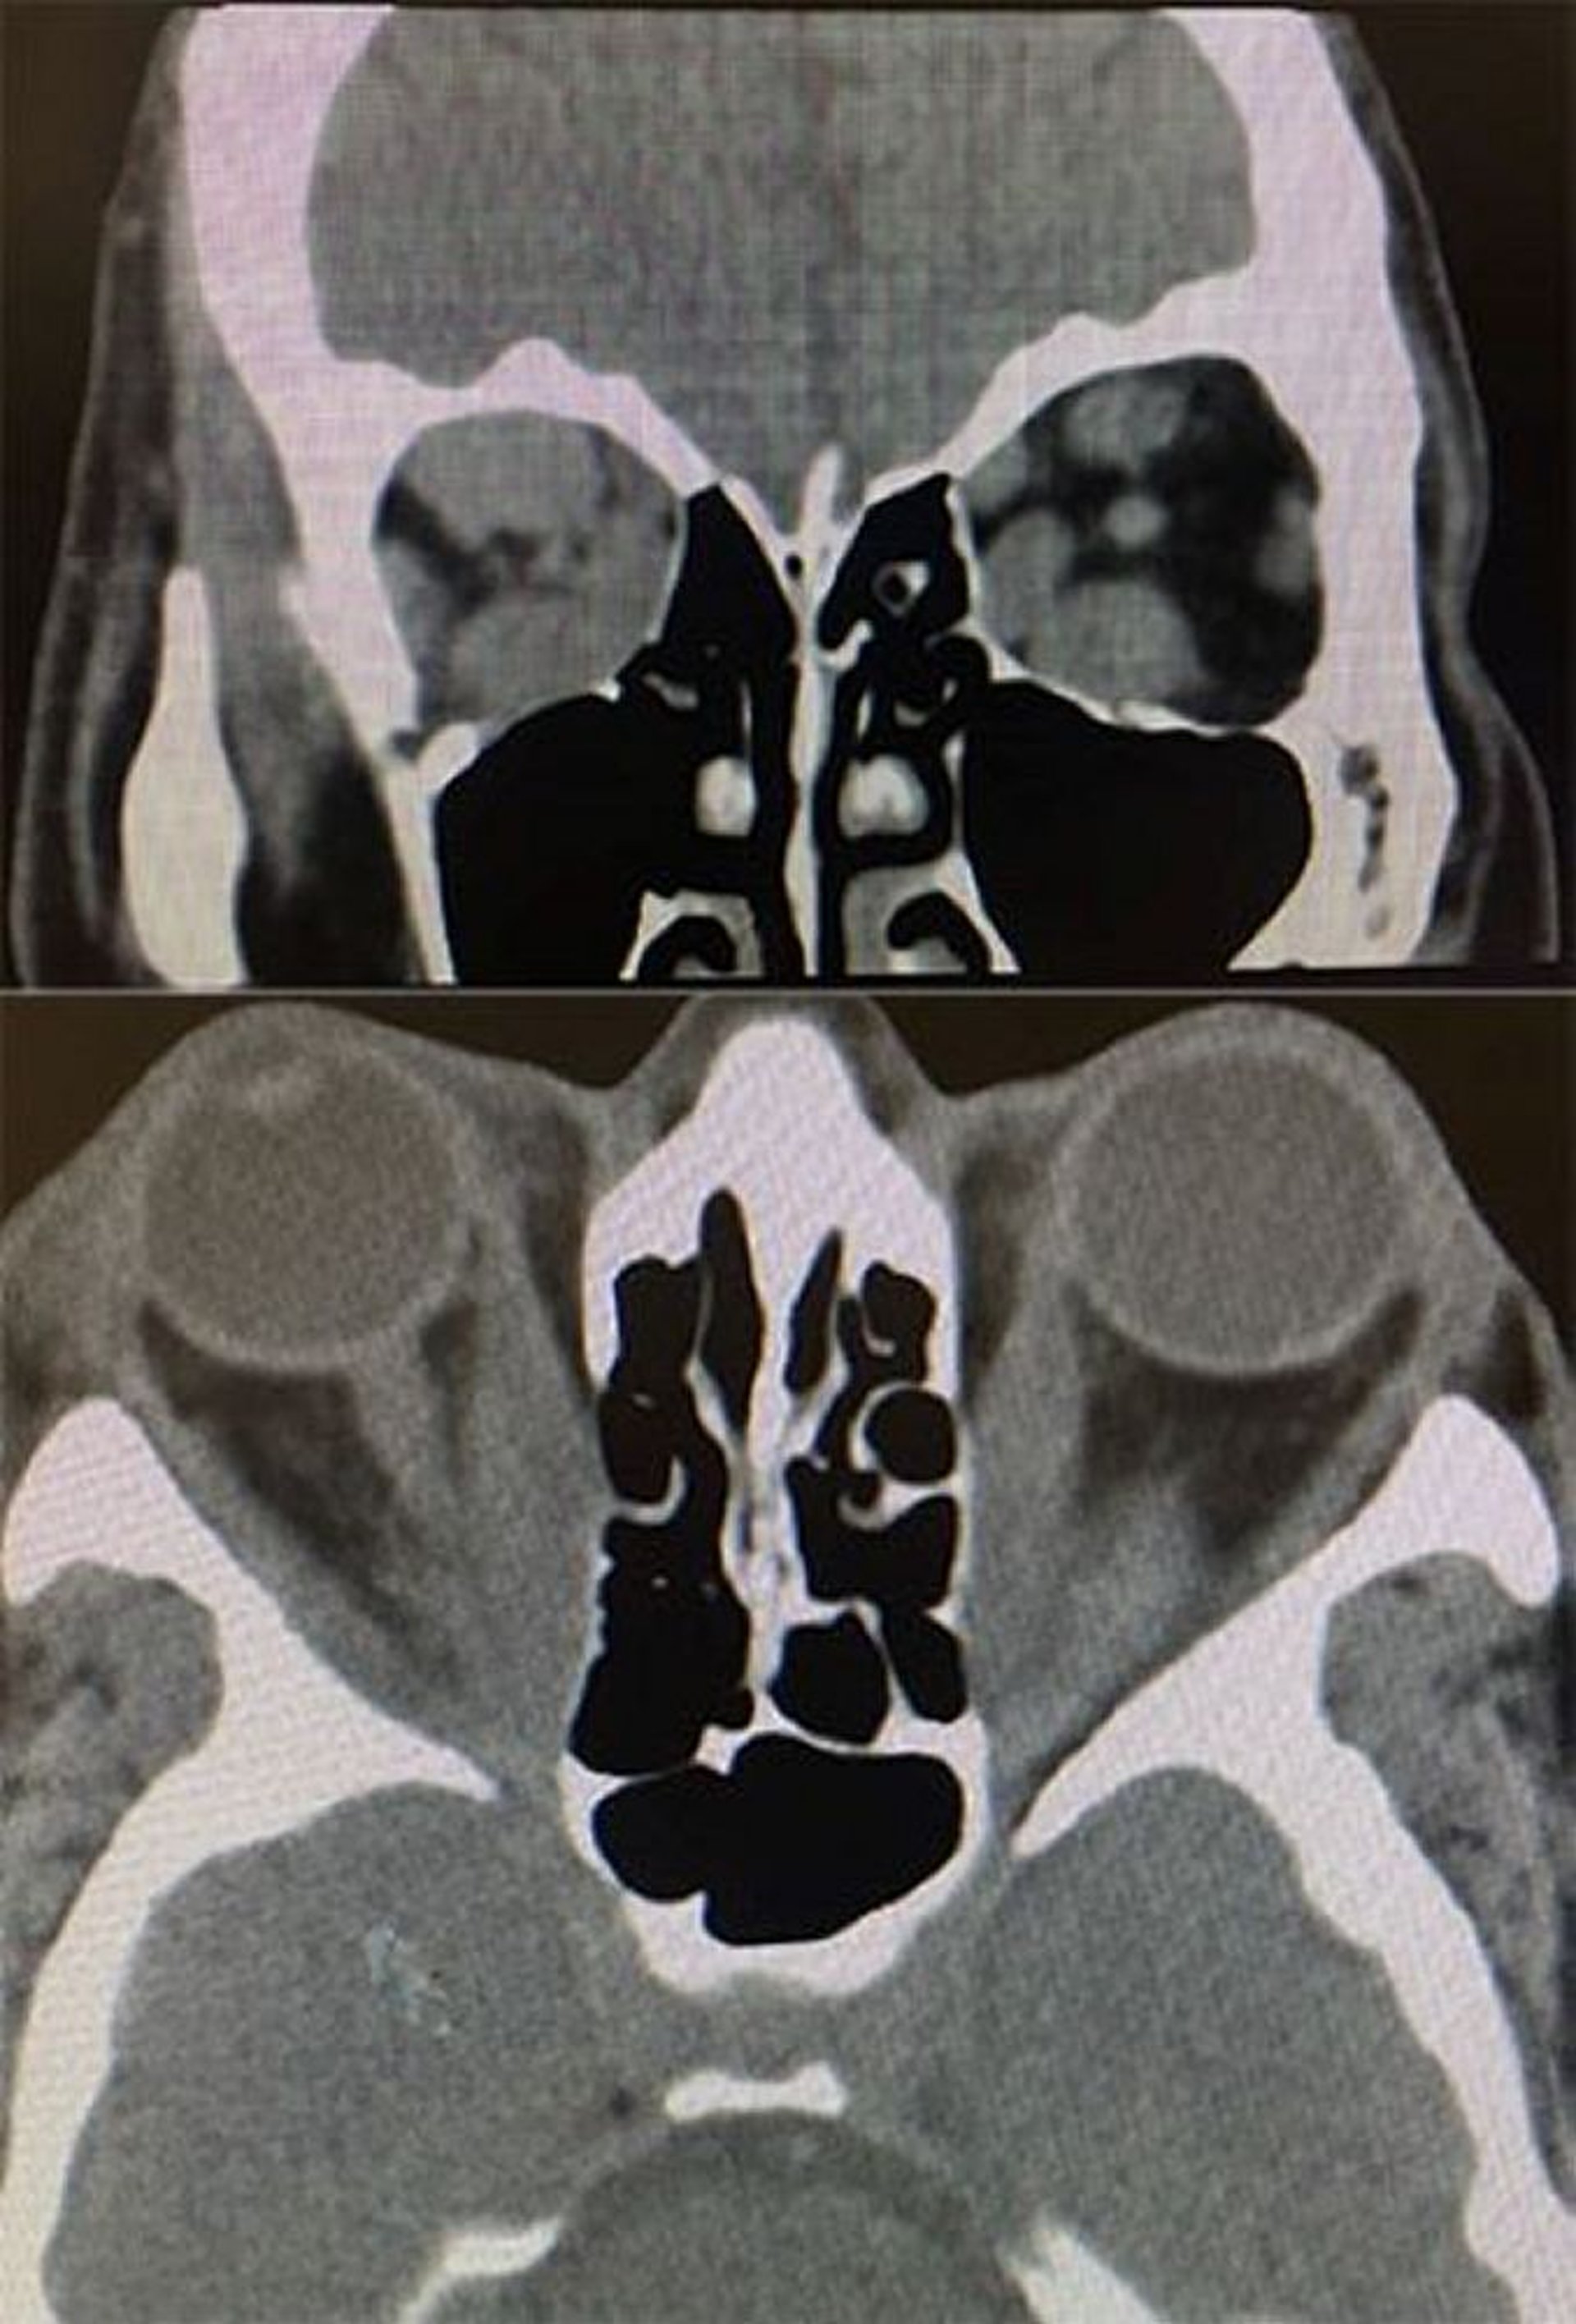

Oftalmopatia tiroidea (TC)

In questa immagine, le scansioni TC assiali e coronali mostrano reperti di oftalmopatia tiroidea. In basso: la TC assiale mostra un ingrandimento del muscolo retto mediale, che risparmia i tendini, bilateralmente. In alto: la TC coronale mostra un ingrandimento dei muscoli inferiori, superiori e del retto mediale più a destra che a sinistra.

Images courtesy of Richard C. Allen, MD, PhD.